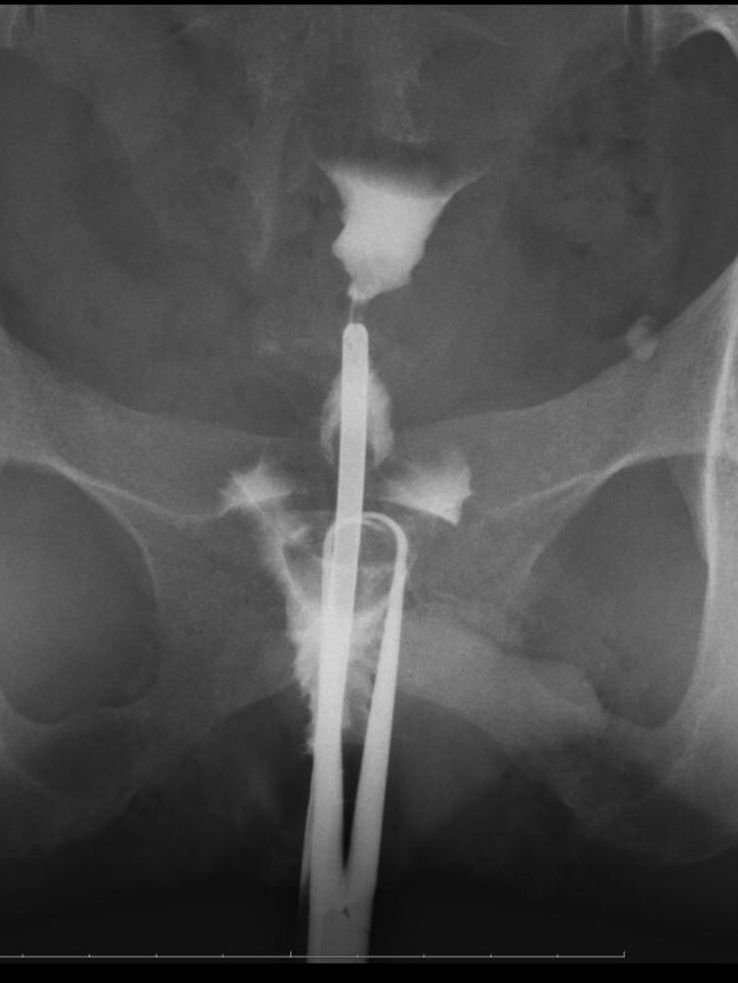

полная непроходимость труб по ГСГ

Сходила на ГСГ. Как итог - непроходимость труб. Контраст вообще не пошел в трубы. Совсем. Ни на сантиметрик. И вообще даже заполнил только половину матки! (снимок)

Врач сказал, что, возможно это полип в центре матки, который перекрывает вход. Но такой огромный полип???

Читала, что может быть спазм и из-за него все сжалось и не пустило контрастное вещество дальше...